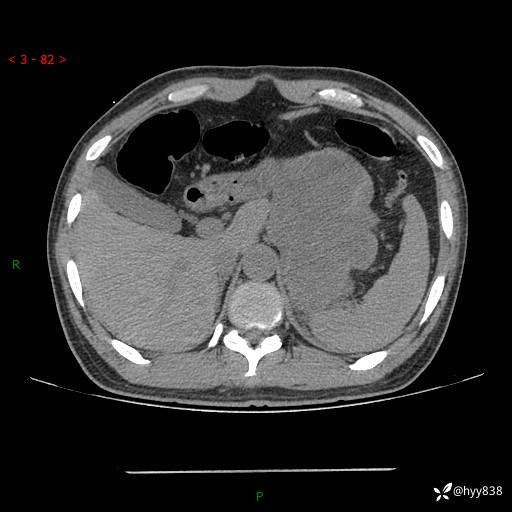

病例39岁/女,左侧腰痛入院。腹腔囊实性肿块,定位、定性---结果公布~

性别:男

年龄:39岁

简要病史:左侧腰痛待查,CT发现腹腔占位

腹部CT平扫+增强